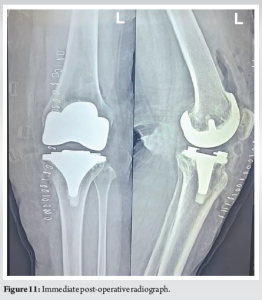

The patient was undertaken for surgery at the earliest possible time, so as to prevent complete perforation of skin and soft-tissue compromise. Medial para-patellar approach through the previous incision was undertaken. Intraoperatively, the locking clip was found to buttonhole through the medial capsule into the subcutaneous tissue (Fig. 6). The polyethylene insert was in its place (Fig. 7) on the tibial baseplate without any evidence of subluxation. The flexion and extension gaps were assessed and were found to be well balanced. The polyethylene insert was removed after subluxating Tibia and no significant wear was seen on either surface. Subluxation of tibia was facilitated by removing the posterior cruciate ligament, performing a quadriceps snip (Fig. 8) and subperiosteal release of anterior portion of superficial medial collateral ligament (Fig. 9) [3]. The CR polyethylene insert was removed and replaced with an anterior stabilizing or deep dish polyethylene insert of 10 mm (Fig. 9-11). Standard post-operative closure was performed. The post-operative course was uneventful with patient achieving full ROM at 1 week without any extension lag. Intraoperatively, samples were collected and sent for culture sensitivity which tested negative.